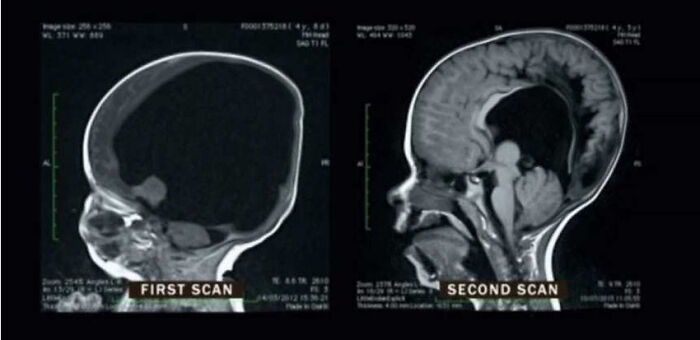

Mri Scans Of A Boy Born With Only 2% Of His Brain And 2 Years Later. His Brain Regrew To 80% Of Its Intended Size And He Only Suffers From Comparably Small Cognitive Deficits Today